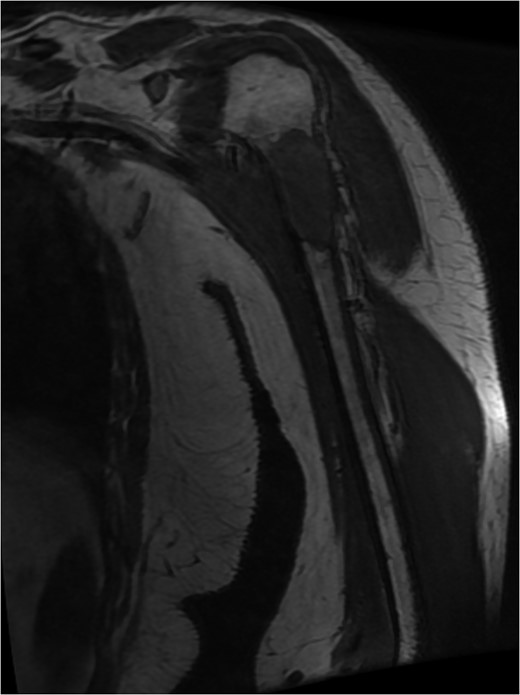

MRI left humerus showed pathological fracture of the neck and proximal shaft humerus, measure 6 × 2.5 × 2.8 cm in maximal dimension. An urgent staging magnetic resonance.